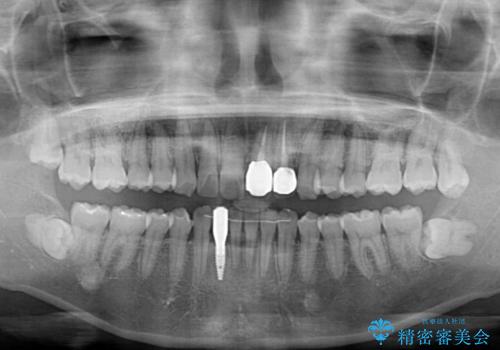

- 下顎前歯が抜けそうとのことで来院された患者様です。

初診の状態ではすぐにでも抜けそうな状態で、インプラントによる補綴治療を行うこととしました。

インプラント治療に際し、前歯の叢生に対する矯正治療を提案したところ、興味を持たれたので、インビザライン・ライトによる矯正治療を行うこととしました。

抜歯後にスペースができると恥ずかしいため、抜歯した歯を接着剤で固定した上で矯正治療を行い、その後インプラントやオールセラミッククラウンの装着を行うこととしました。